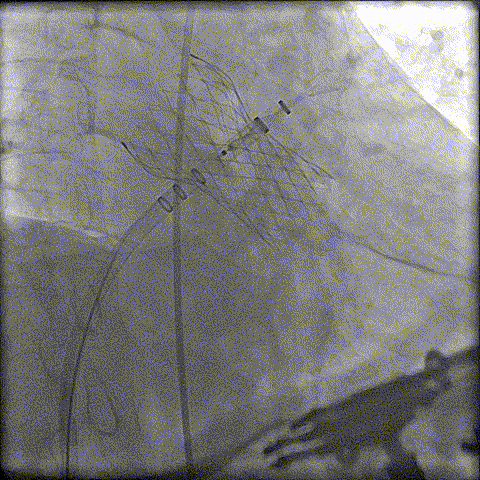

术前CT分析判断该心耳为反鸡翅型左心耳,选择偏下略偏前的位置进行房间隔穿刺。在工作体位造影后,可见左心耳内梳状肌发达,反鸡翅叶显影清晰,鞘管轴向佳。经DSA测量左心耳开口18mm深度17mm,结合TEE测量数据,综合考虑选用WATCHMAN24mm封堵器进行封堵。在展开封堵器时利用在体内借深度技巧,保证封堵器封堵位置合理。封堵器展开后经造影检查封堵器封堵效果理想,牵拉试验稳定。超声评估封堵器各角度无残余分流,位置理想,满足PASS原则,随即释放封堵器,一站式手术顺利结束。

左心耳造影

封堵器缓慢展开

即刻造影

释放封堵器